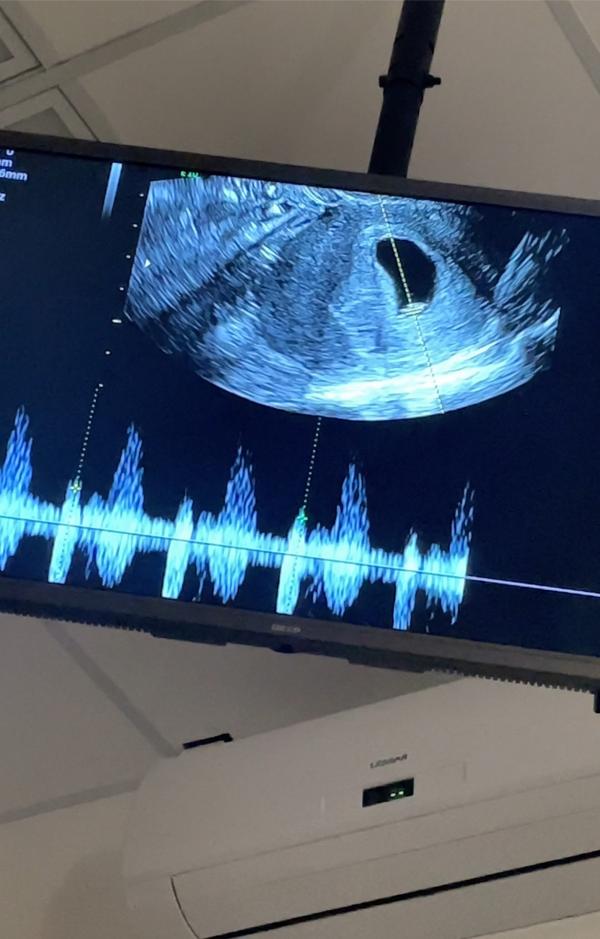

УЗИ 7,1 неделя (6,5 по ктр )

Ктр 7,4мм (6,5 недель по КТР)

ЧСС +123

ПЯ 24мм

ЖМ 4мм